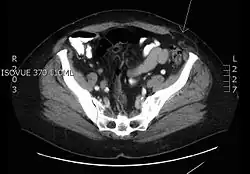

| Transverse CT image of the abdomen in a patient with a Spigelian hernia (arrow). | |